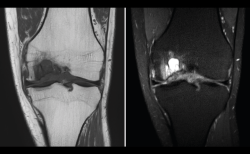

5. Tumores: óseos y de partes blandas

Figura 55. Corte de secuencia coronal T1 y STIR de resonancia magnética de rodilla: masa metafisaria tibial con fractura sobreañadida en la epífisis tibial proximal.

La RM es útil en las lesiones tumorales para determinar la extensión local (Figuras 55 y 56).

Figura 56. Corte de secuencia T2 Fat-Sat de resonancia magnética de rodilla: masa con intensidad de señal de grasa por gran lipoma localizado en la parte alta de la bursa suprapatelar.